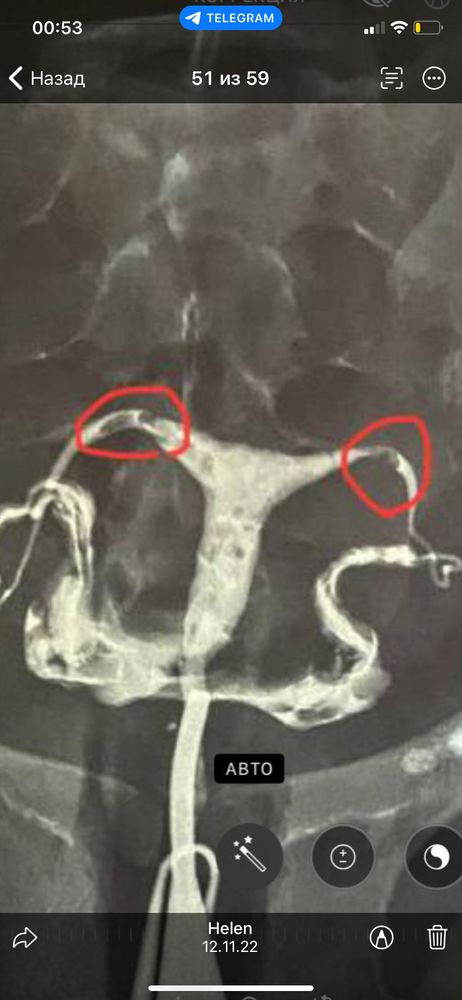

планирую беременность Москва

Влада, вообще гсг показало затемнения, но ни мой репродуктолог , ни врач, который проводил гсг и давал заключение не подумали что это полипы. Жидкость в трубах пролетела моментально и сразу расплылась внутри, мне небыли сильно больно. Они подумали, что это просто затемнения, жидкость так пошла, но нет. Как потом Оказалось, такие полипы . Вот фото моего гсг, если интересно. Изображение